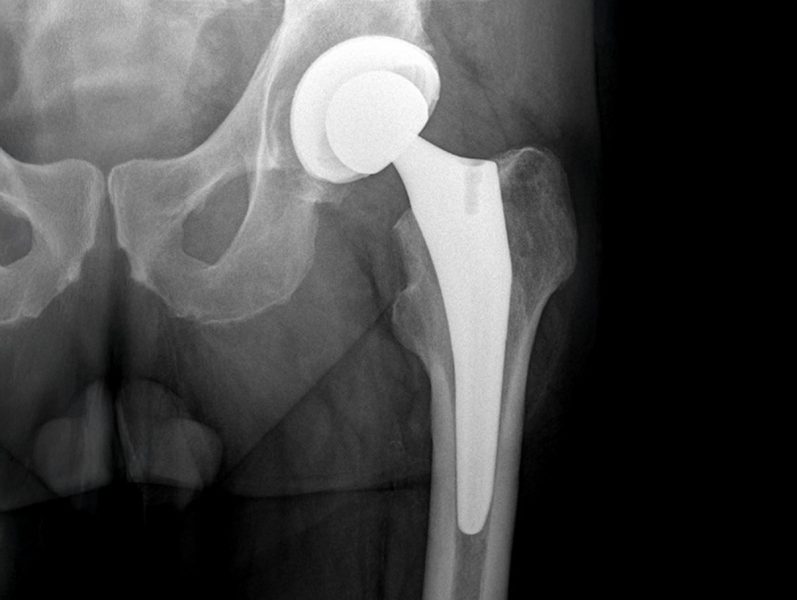

In unserer Abteilung werden primäre und Revisionsendoprothesen an Hüft –, Knie – und Schultergelenken durchgeführt.